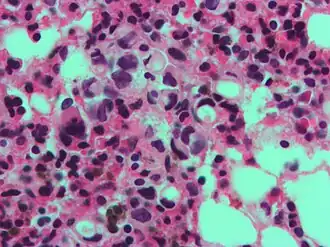

Signet ring cell, as seen in a case of colon adenocarcinoma with mucinous features, showing a tumor cell with a vacuole of mucin. H&E stain.

In histology, a signet ring cell is a cell with a large vacuole. The malignant type is seen predominantly in carcinomas. Signet ring cells are most frequently associated with stomach cancer,[1] but can arise from any number of tissues including the prostate,[2] bladder, gallbladder,[3] breast, colon,[4] ovarian stroma and testis.[5]

The name of the cell comes from its appearance; signet ring cells resemble signet rings. They contain a large amount of mucin, which pushes the nucleus to the cell periphery. The pool of mucin in a signet ring cell mimics the appearance of a finger hole and the nucleus mimics the appearance of the face of the ring in profile.